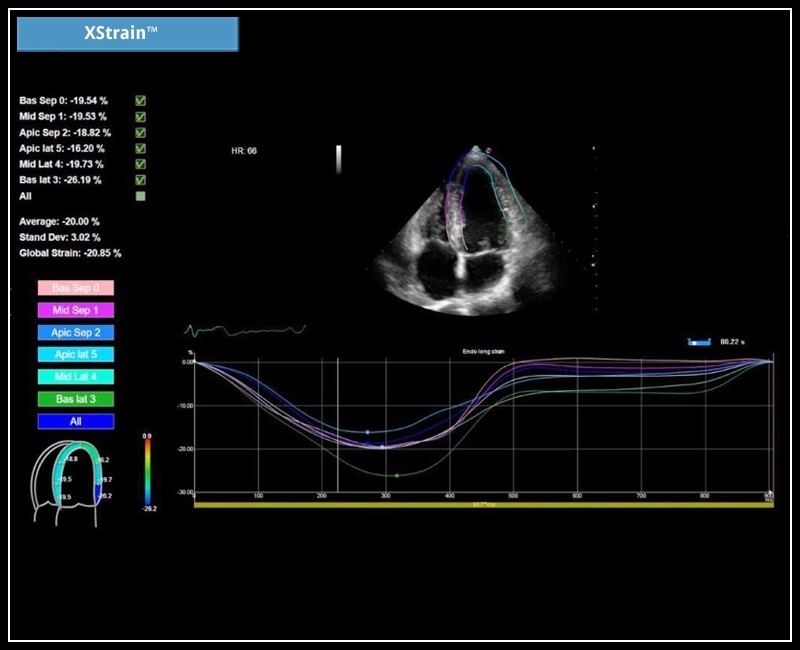

MyLab™C25 - Xstrain

MyLab™C25 - Xstrain

MyLab™9 Platform - XStrain™ 2D speckle tracking technologies for global and regional function

MyLab™9 Platform - XStrain™ 2D speckle tracking technologies for global and regional function

MyLab™Sigma - Left Ventricle XStrain 2D analysis

MyLab™Sigma - Left Ventricle XStrain 2D analysis

MyLab™X5 - XStrain

MyLab™X5 - XStrain

MyLab™X6 - XStrain

MyLab™X6 - XStrain

MyLab™X7 - XStrain

MyLab™X7 - XStrain